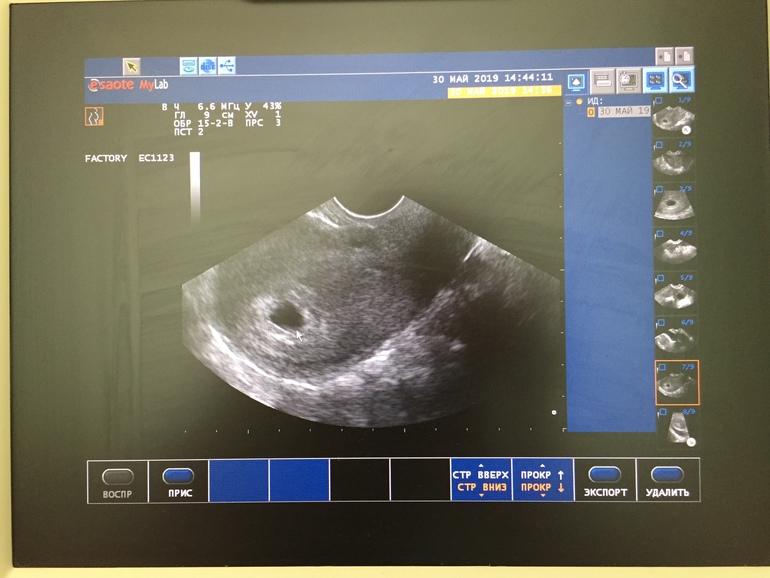

Сегодня 14 недель и 1 день и проснулась ночью от ноющей боли, думала пройдёт, но уже обед и боль такая же ... поясница вроде тоже тянет, психологически сложно...